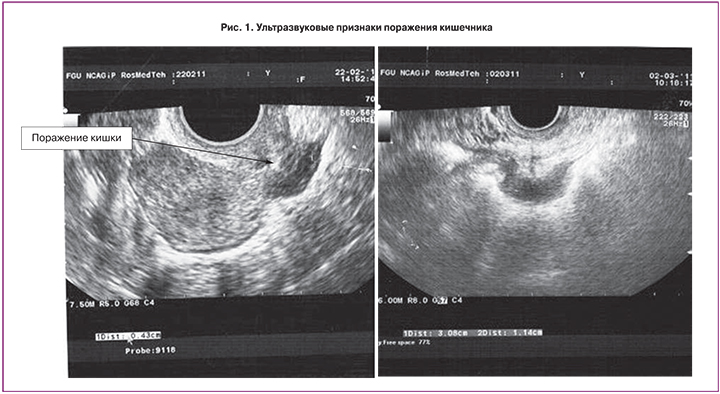

Поражения кишечника в 91–98% могут быть диагностированы при трансвагинальном УЗИ и до 100% – при трансректальном [11]. Характерными акустическими признаками ГИЭ являются:

- плотное образование в ректовагинальной перегородке и за ее пределами;

- неоднородная эхоструктура образования;

- неровные и нечеткие контуры границ образования (рис. 1).